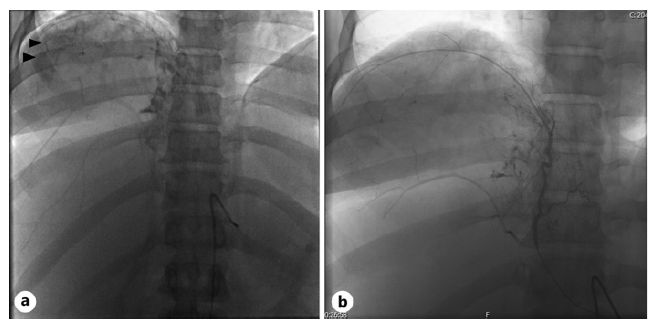

The case was discussed with Interventional Radiology and the Hepato-Biliary-Pancreatic Surgical team, and an urgent arterial embolization was performed, halting the bleeding (shown in Fig. 2). She was transfused with a total of 3 units of red blood cells, resulting in a final hemoglobin level of 8.3 g/dL.

Fig. 2 Angiography images before (a) and after (b) embolization. Angiography was used to identify the vascular supply to the tumor, with the phrenic artery showing significant vascular supply (arrows). Supra-selective arterial embolization of the right and medium hepatic and phrenic arteries with polyvinyl alcohol embolic particles was performed, with cessation of bleeding.